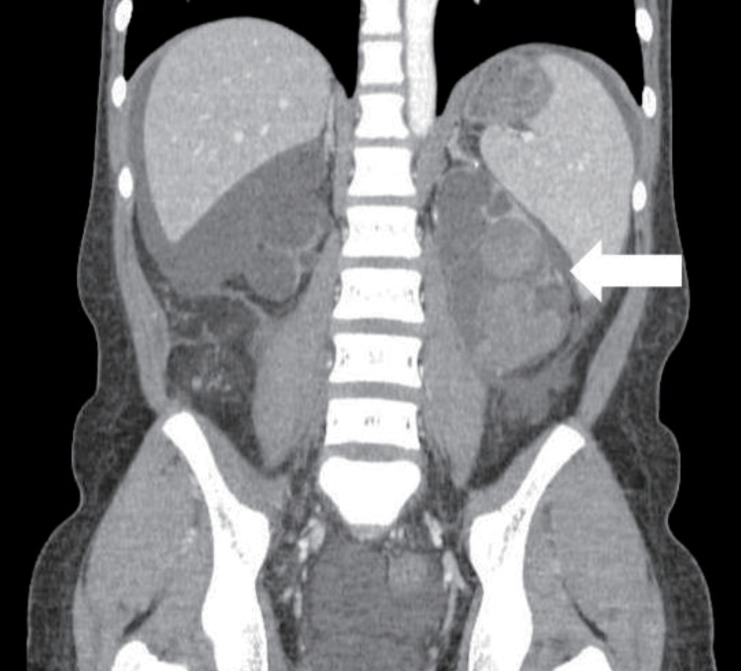

A-15-year-old girl was admitted with left flank pain and gross hematuria for several days. Four years ago, she was diagnosed as end-stage renal disease due to dysplastic kidneys which was multicystic dysplastic kidney in right side and was dysplastic kidney with severe hydronephrosis in left side. She underwent cadaveric kidney transplantation. However, because chronic allograft dysfunction has occurred, she has been undergoing peritoneal dialysis for 3 months. She had received oral immunosuppressant therapy during kidney transplantation state, and it was stopped when the peritoneal dialysis was started. Her blood pressure was 147/104 mmHg, heart rate was 112 beats/min and respiratory rate was 22 beats/min. She looked acutely ill and physical examination revealed severe tenderness on the left costovertebral angle, but no pitting edema. The laboratory findings on admission were hemoglobin 6.3 g/dL, hematocrit 18.7%, white blood cell count 5,640/µL (lymphocyte 78% neutrophil 17%) and platelet 144,000/µL. The blood chemistry showed total protein/albumin 6.8/2.6 g/dL, sodium/potassium 132/4.0 mmol/L, calcium/phosphorus 7.3/3.5 mg/dL, blood urea nitrogen/creatinine 43/13.1 mg/dL, erythrocyte sedimentation rate 53 mm/hr, and C-reactive protein 2.2 mg/dL. Coagulation blood test was prothrombin time 105%, partial thromboplastin time 30.5'', international normalized ratio 1.0. Her urine showed gross hematuria with blood clots and protein (4+) occult blood (3+) on dipstick. The analysis of dialysate was normal. Computerized tomography of her abdomen revealed encapsulated intrapelvic hematoma in the left kidney (Fig. 1). She was given red blood cell transfusion and with conservative therapy, flank pain and gross hematuria were improved. Follow-up serial hemoglobin level was remained and her blood pressure was maintained within the normal range. Follow-up abdominal computerized tomography showed as renal pelvic hematoma of the same size. She was discharged with improved condition. At the outpatient department, she had neither fever nor pain, but complained of intermittent gross hematuria with blood clot and her anemia was not improved. Ten days after discharge, follow-up laboratory findings showed a reversed albumino-globulin ratio (total protein, 6.6 g/dL; albumin, 1.9 g/dL; globulin, 4.7 g/dL; albumin/globulin ratio, 0.4) and this finding was sustained for two months in spite of no evidence of infection or inflammation. Serum electrophoresis was compatible with polyclonal gammopathy, which showed an increased component with alpha-1 and gamma fraction (Fig. 2). Thereafter, a massive gross hematuria was recurred and anemia was persisted. We performed the embolization of the left renal artery, two months after when the renal cystic hemorrhage began. The continuous bleeding was solved and also, albumino-globulin dissociation was normalized a month after renal artery embolization was done (Fig. 3).

Fig. 1

X-ray scan showing a hematoma in renal cysts of the left kidney (arrow).